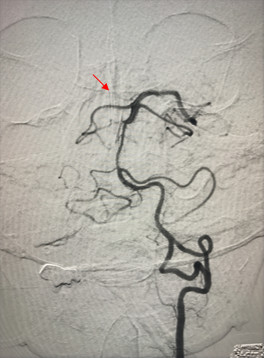

外侧型、Saltzman Ⅲ型

起自于右侧颈内动脉岩段与破裂孔段之间

供应双侧小脑上动脉及对侧大脑后动脉:

7.6mm×9.9mm

Kink 46°